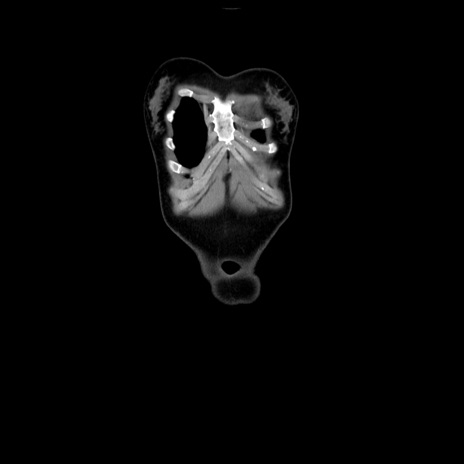

MRI(4日後)